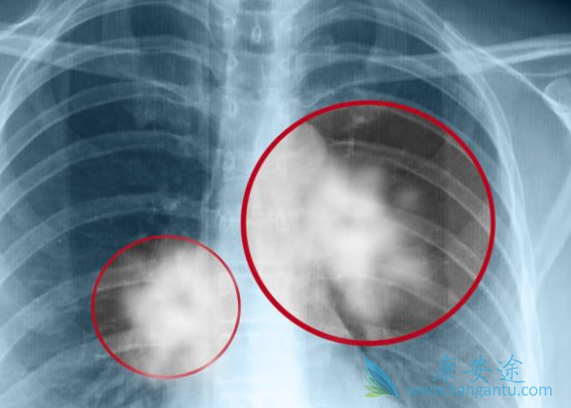

靶向药物的出现是身患肺癌患者的一线希望,是生命的曙光,特别是对于ALK突变患者来说,使用ALK TKI能够带来更长的生存期。恩沙替尼的出现为这些患者的治疗锦上添花。